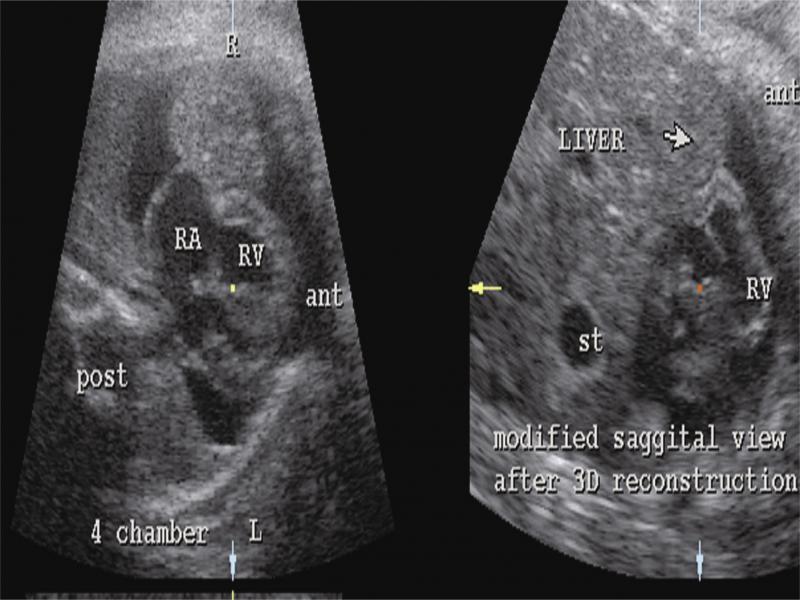

Retrospective offline reconstruction from the echocardiography examination. Left-side picture: referral image in which the pericardial tumor with pericardial effusion is seen (corresponding to the Fig. 1). ant – anterior, post – posterior, RA – right atrium, RV – right ventricle, L – left, R – right. Right-side picture: modified sagittal view reconstruction from the STIC volume. The “tumor” is identified as part of the liver herniating into the pericardial cavity (arrow). st – stomach